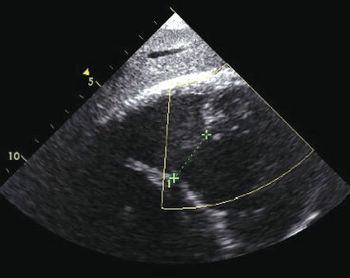

Myocarditis, postpericardiotomy syndrome, double aortic arch, heart-hand syndromes, stroke, cardiac valvulopathy, hemochromatosis, myocardial rupture-these visual presentations cover a range of heart diseases and related problems.